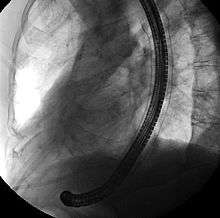

Biliary SEMS are used to palliatively treat tumours of the pancreas or bile duct that obstruct the common bile duct. They are inserted at the time of ERCP, a procedure that uses endoscopy and fluoroscopy to access the common bile duct. The bile duct is cannulated with the assistance of a guidewire and the sphincter of Oddi that is located at its base is typically cut. A wire is kept in the bile duct, and the SEMS is deployed over the wire in a similar fashion as esophageal stents. The location of the SEMS is confirmed by fluoroscopy.[17]